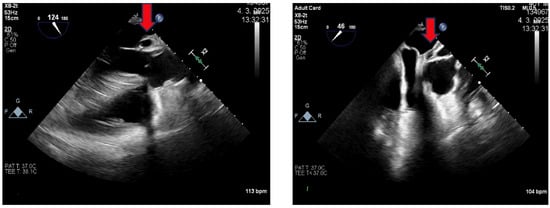

2. Case Presentation